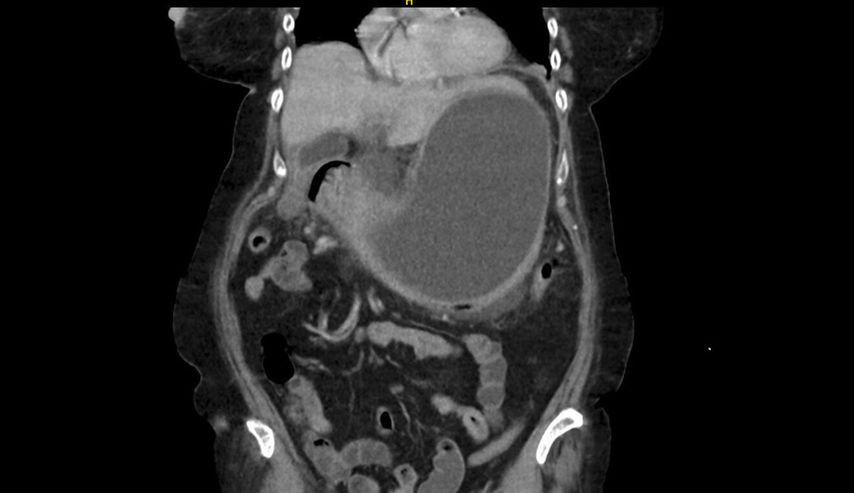

In der durchgeführten Computertomografie des Abdomens (Abb.1) zeigt sich der Verdacht auf einen hohen Ileus mit prall sekretgefülltem, distendiertem Magen (25cm kraniokaudal). Weiters stellt sich die Magenwand auf bis zu 17mm verdickt dar – mit intramuralen Lufteinschlüssen, insbesondere entlang der großen Kurvatur. Eine Ausgangsstenose im gastroduodenalen Übergang wird suspiziert. Rasch wird eine nasogastrale Sonde eingebracht, die trotz korrekter Lage kein Sekret fördert.

Im Rahmen der Narkose wird eine Sonografie des Abdomens ergänzt, in der sich nun der Verdacht bestätigt, dass die große Fluidokollektion nicht im Magen, sondern intramural in der ventralen Magenwand liegt.

Es folgen eine sonografisch gezielte Punktion und perkutane Pigtail-Drainageanlage in die Fluidokollektion (Abb.3). Prompt entleeren sich 2,8l Pus. Die Drainage wird regelmäßig gespült und für 10 Tage belassen. In der Kultur des Punktats können Streptococcus anginosus und Klebsiella pneumoniae nachgewiesen werden, die initial eingeleitete Antibiose mit Piperacillin/Tazobactam wird antibiogrammgerecht umgestellt. Eine Kontrollgastroskopie (Abb.4) zeigt einen unauffälligen Befund am Pylorus und im Bulbus sowie in der Pars descendens duodeni, zahlreiche Biopsien der Magenschleimhaut ergeben eine geringgradige chronische, inaktive Corpusgastritis mit mukosalem Ödem.